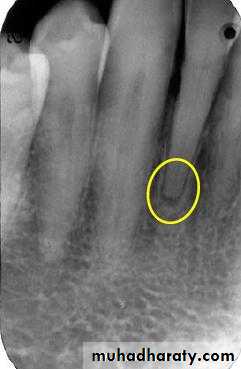

Radiographic Features:

Most lesions are discovered on routine radiographic examination.A well-defined radiolucency of bone apical to the offending tooth. Loss of the apical lamina dura.

The lesion may be circumscribed or ill defined.

The size is variable.

Cyst of long standing may undergo an acute exacerbation which lead to abscess formation.Radiographic Features.

in most cases is identical to periapical granuloma,but, the cyst may be of greater size than the granuloma.Occasionally the apical periodontal cyst exhibits a thin, radiopaque line around the periphery of the radiolucent area, and this indicates a reaction of the bone to the slowly expanding mass.